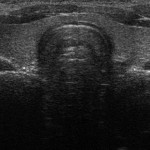

FOTO

Ecografía de tiroides. En algunos casos es necesario realizar biopsias para determinar si los nódulos detectados son malignos.